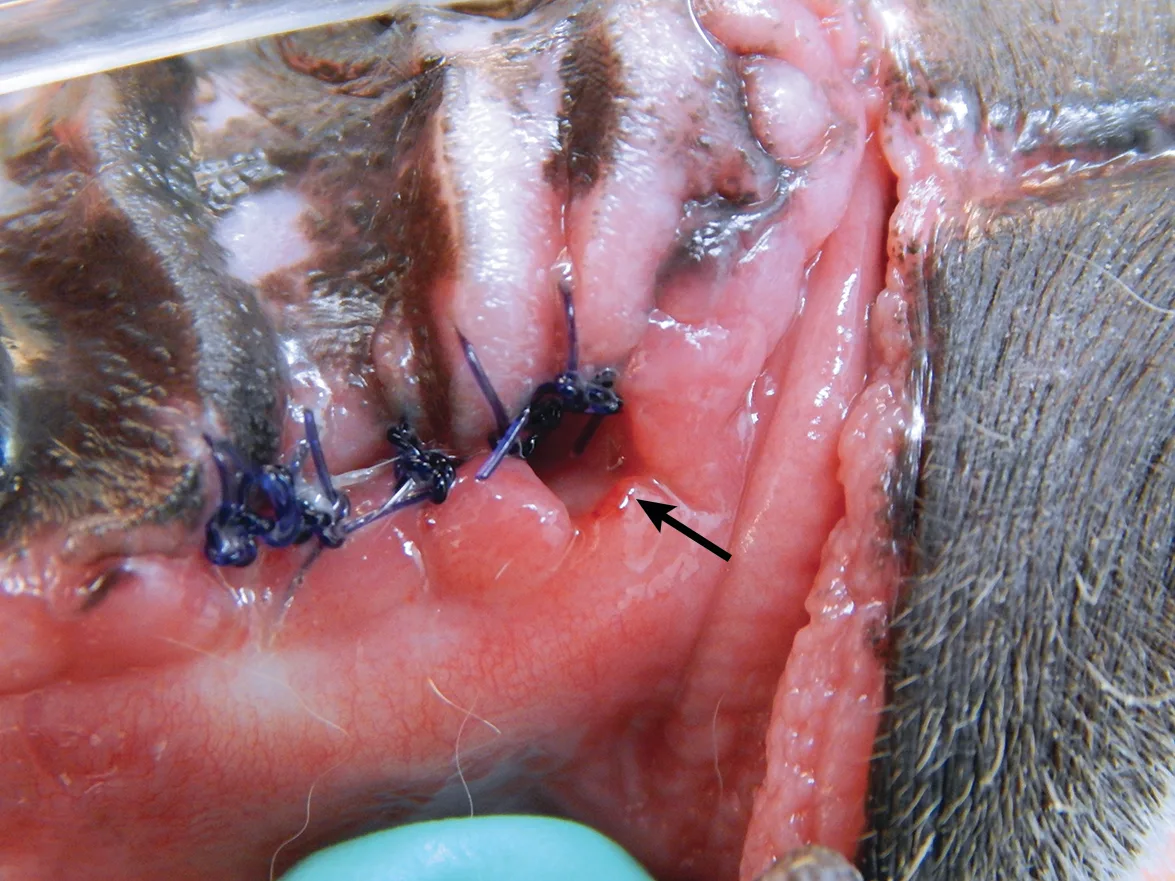

Gingival tissue can be inadvertently damaged during extraction (Figure 2), most commonly as a result of clinician inexperience or inadequate training in proper surgical extraction techniques. Gingival tissue manipulation training should be a prerequisite for performing surgical dental extractions.

Wound dehiscence (arrow) caused by wound tension and iatrogenic tissue damage in a cat presented for surgical repair of the maxillary canine tooth extraction site